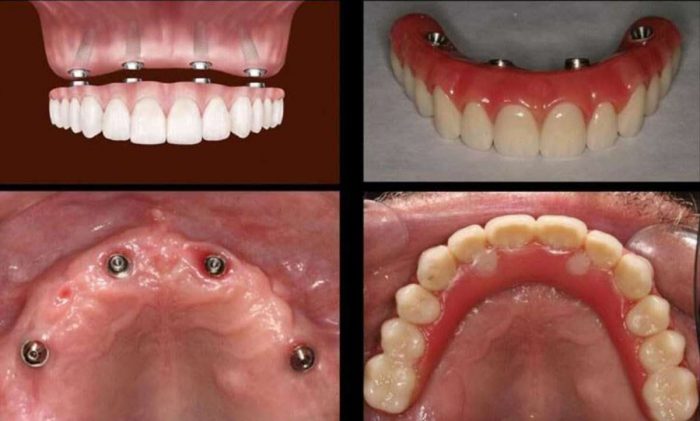

Dental implants are a popular choice for tooth replacement. If you are considering Dental Implants in Houston Midtown, VIP Dental Implants is the perfect place for you. We offer a variety of dental implant options, so you can choose the one that is right for you. Contact us today to schedule a consultation and learn more about dental implants.